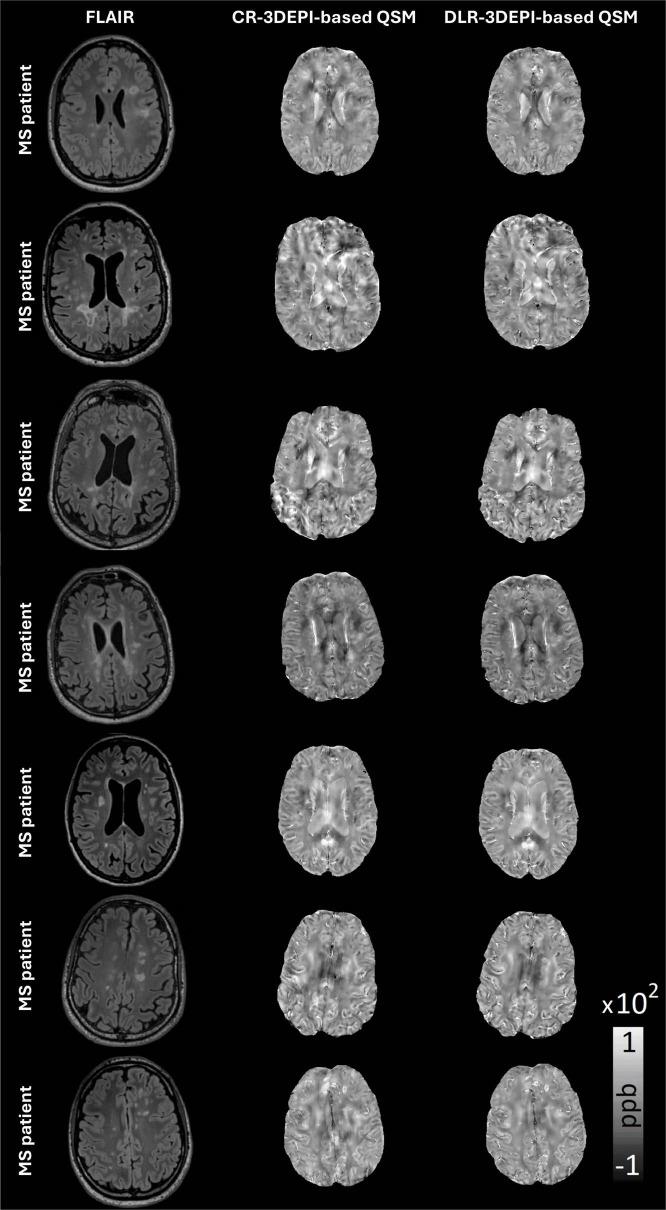

3T MRI 3DEPI-data were acquired on seven MS patients and offline-reconstructed using CR and DLR. FLAIR segmentation. Two experts, independently and method-blinded, rated lesion-wise the CR- and DLR-3DEPI-derived QSM, assessing the confidence in identifying paramagnetic rim lesions (PRLs), central vein sign (CVS), QSM hyper/isointense lesions and image quality. Gradient-recalled-echo (GRE), 2- and 1-average 3DEPI (acquisition time: 7:02, 3:44, and 1:56 min, respectively) from a healthy individual were offline-reconstructed using CR and DLR. Derived QSM maps were compared visually and quantitatively.

Deep learning reconstruction-3DEPI-based QSM was rated significantly higher for the confidence in identification of the MS-specific biomarkers (hyper/isointense lesions: < 0.001, CVS: = 0.01) and overall image quality ( < 0.001), compared to CR-3DEPI-based. Inter-method agreement was high for both raters (Cohen's κ = 0.98/0.92), suggesting that DLR improves the quality without changing the rater's perception of the individual QSM-related clinical findings. Additionally, QSM derived from fast DLR-3DEPI with a fourfold acquisition-time reduction compared to GRE, exhibited excellent visual and quantitative consistency with GRE-based QSM.

Our results constitute a first demonstration of the enhanced quality and clinical utility of the DLR-3DEPI-based QSM in MS.